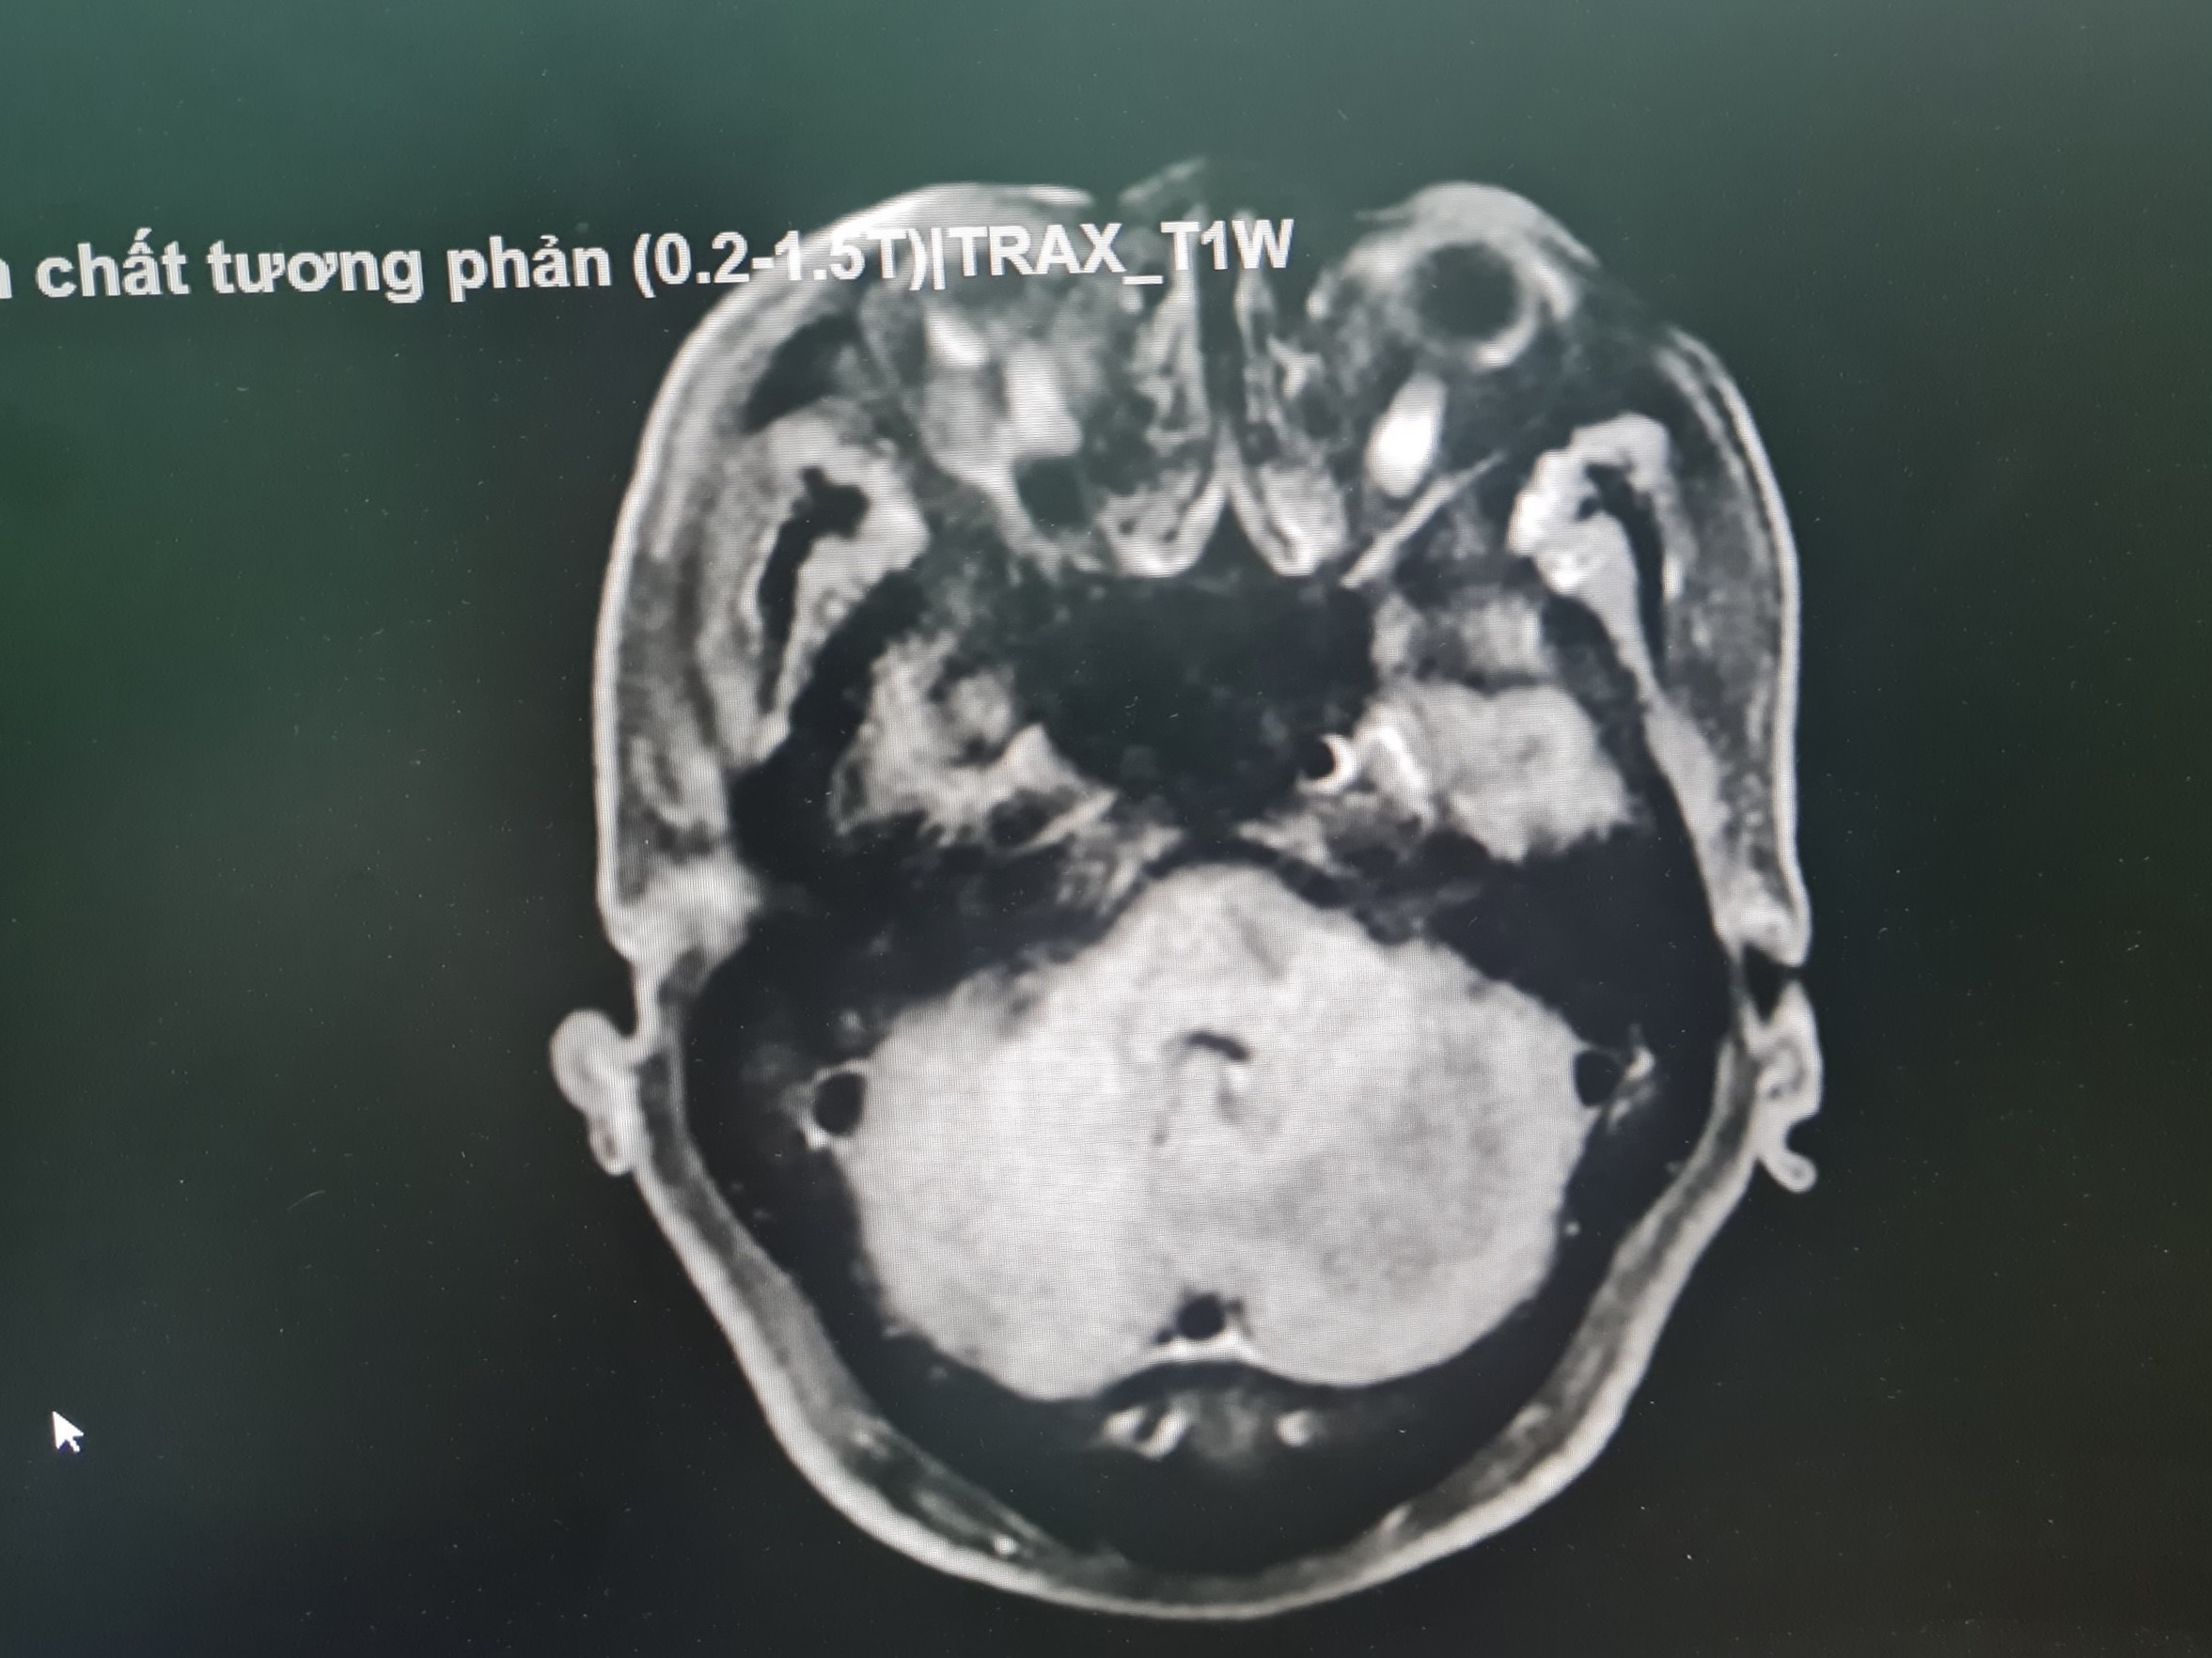

Tại Bệnh viện Đa khoa tỉnh Thanh Hóa, qua thăm khám, làm các xét nghiệm cận lâm sàng và chụp MRI sọ não, các bác sỹ phát hiện bệnh nhân có u tiểu não bên trái kích thước 3x2cm. Bệnh nhân ngay sau đó được hội chẩn và chuyển về khoa Phẫu thuật Thần kinh – Lồng ngực điều trị.

Hình ảnh chụp MRI sọ não có tiêm thuốc cản quang phát hiện U não của bệnh nhân T.V.C